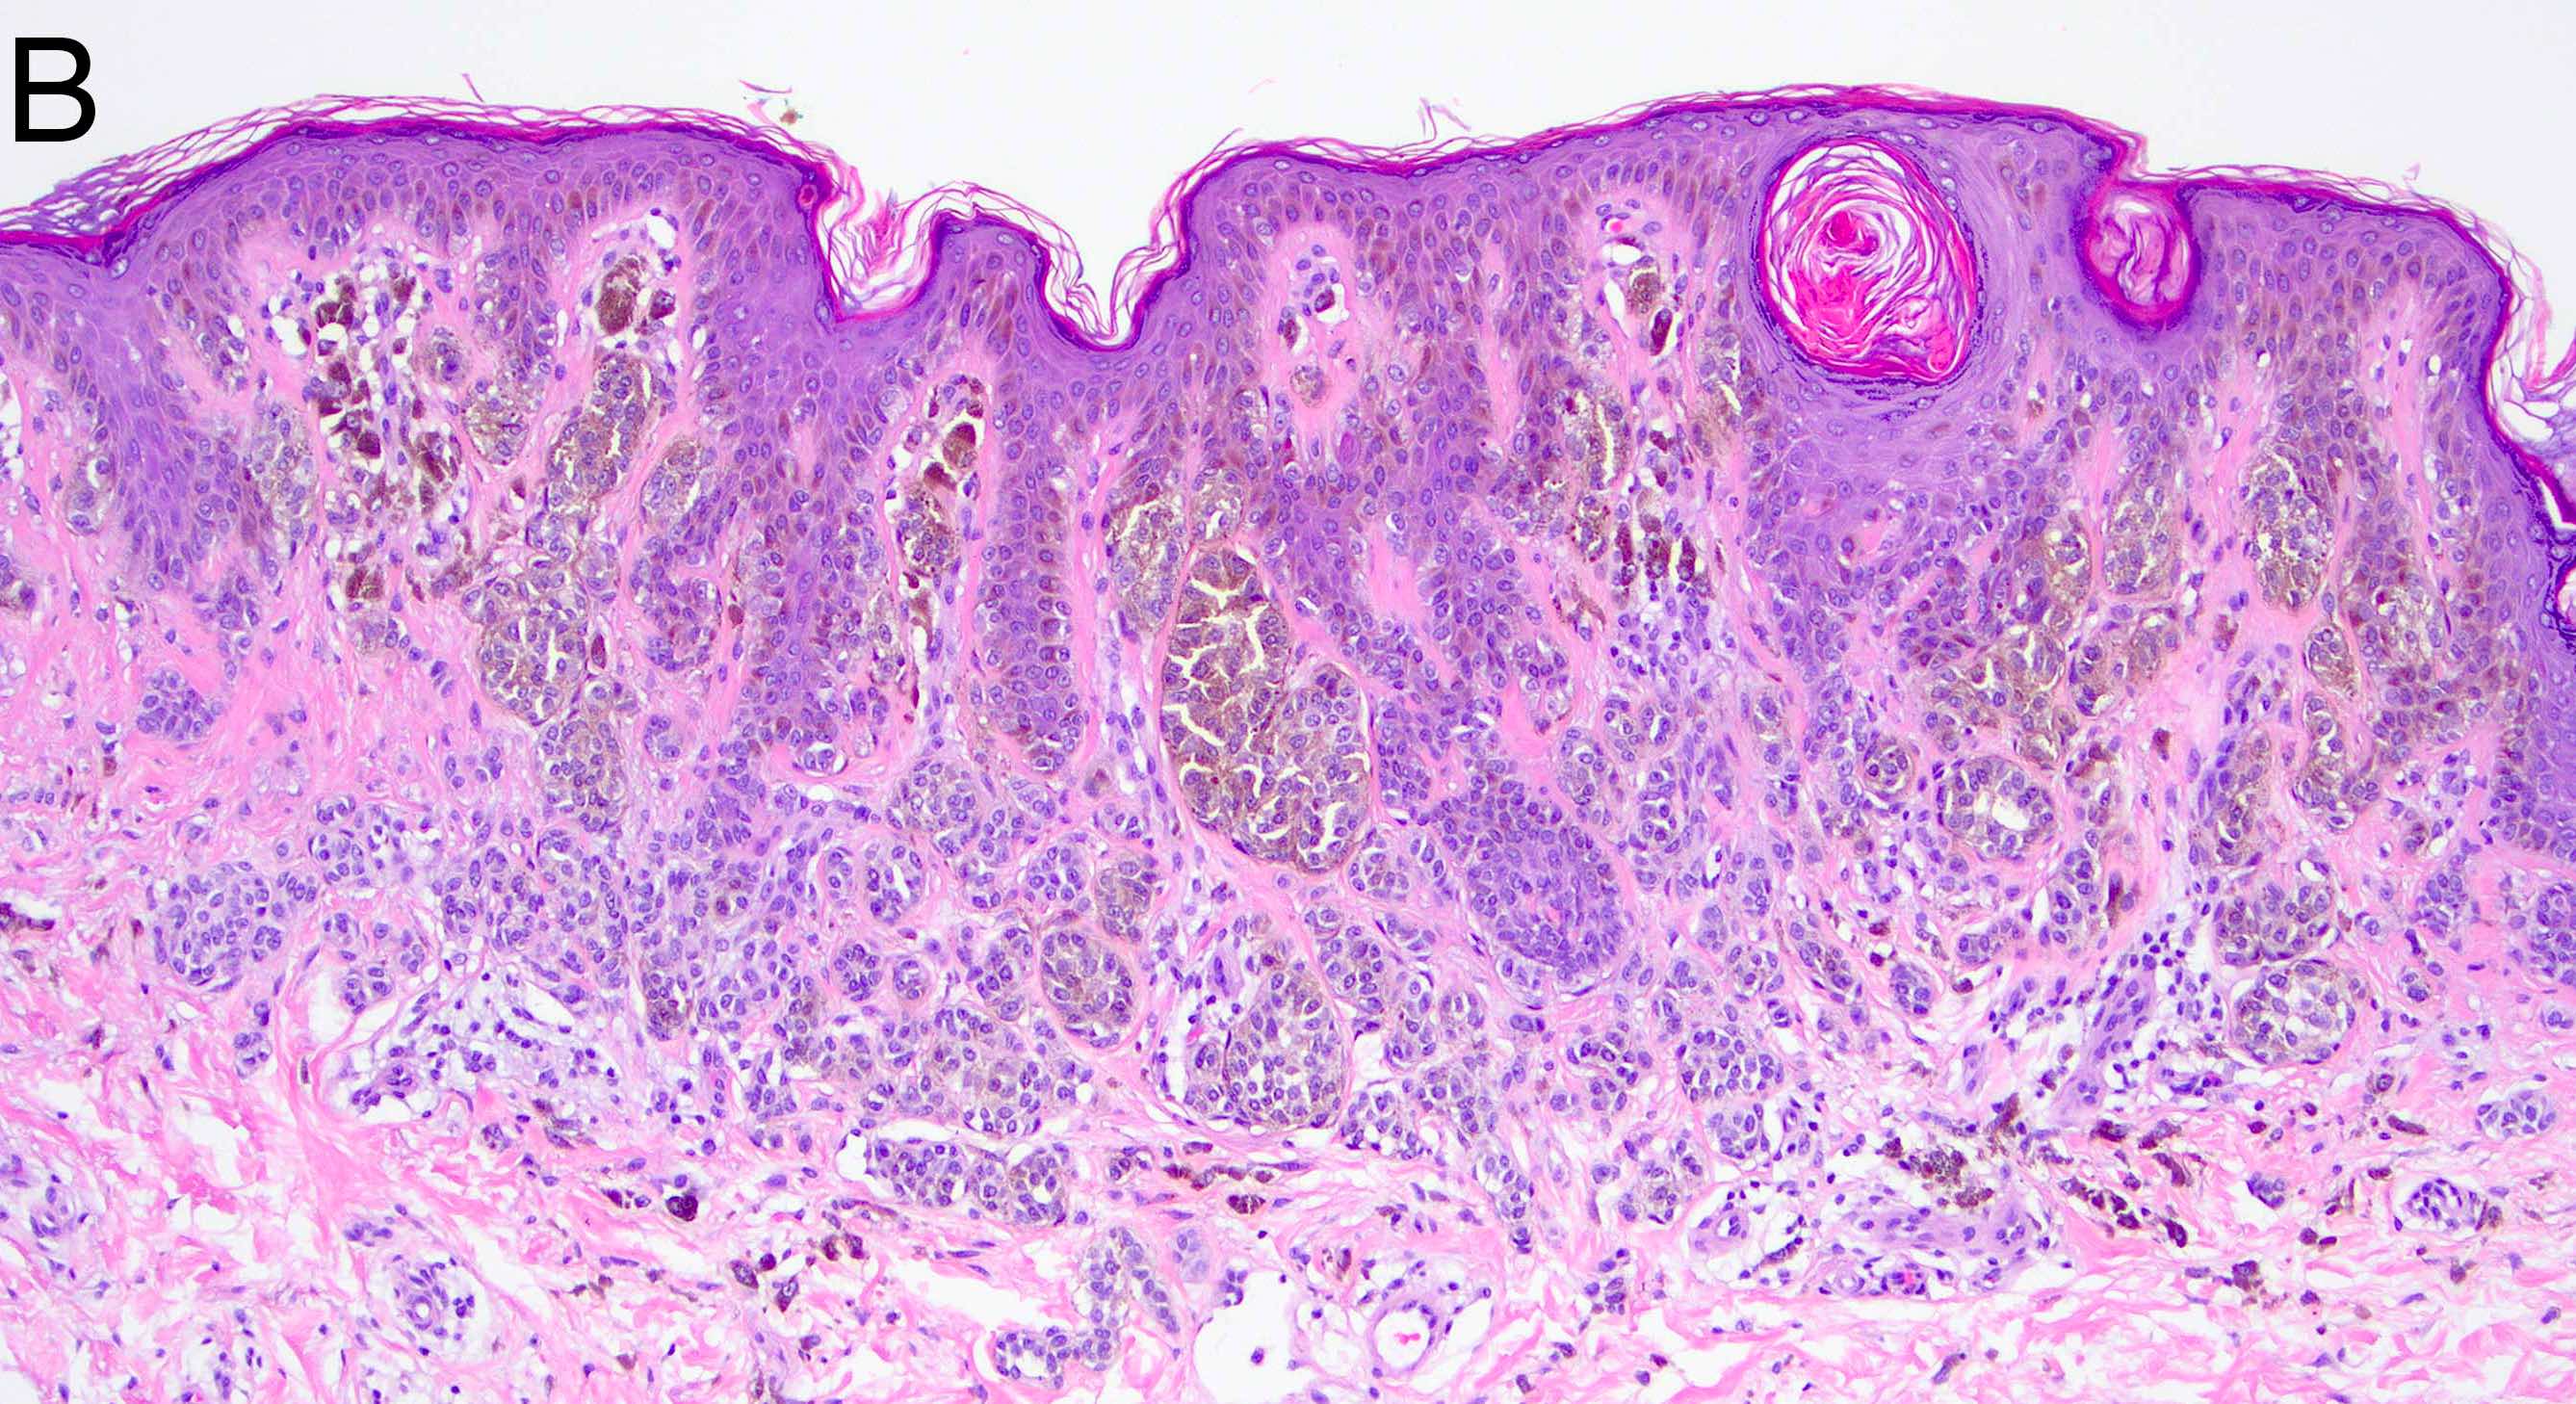

- Melanocytic nevi of the breast (Am J Dermatopathol 2016;38:867):

- May contain large irregular dyshesive nests in close proximity to one another

- Junctional nests may not be centered and can be placed within inter-rete spaces and along sides of rete

- Nests may have variable pigmentation (results in globules seen on dermoscopic exam)

- Nests may have prominent horizontal streaming resulting in rete blunting or epidermal effacement

- Cytologic atypia is common

- Maturation with melanocyte descent should be retained

Microscopic (histologic) images